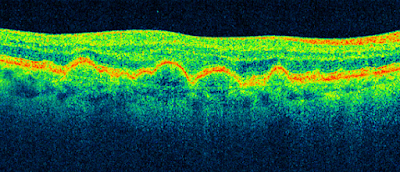

| An OCT scan of the other eye, in the same patient. The natural valley or dip for central vision, without any oedema or fluid filled spaces. |

It is important to rule out macula oedema as the cause of reduced vision post surgery. Patients should undergo a thorough slit lamp examination and have an OCT scan. Which immediately shows any fluid or swelling in the macula, which is the part of the retina used for central vision. Macula oedema or fluid in the retina is a possible complication of surgery and should be checked an monitored.